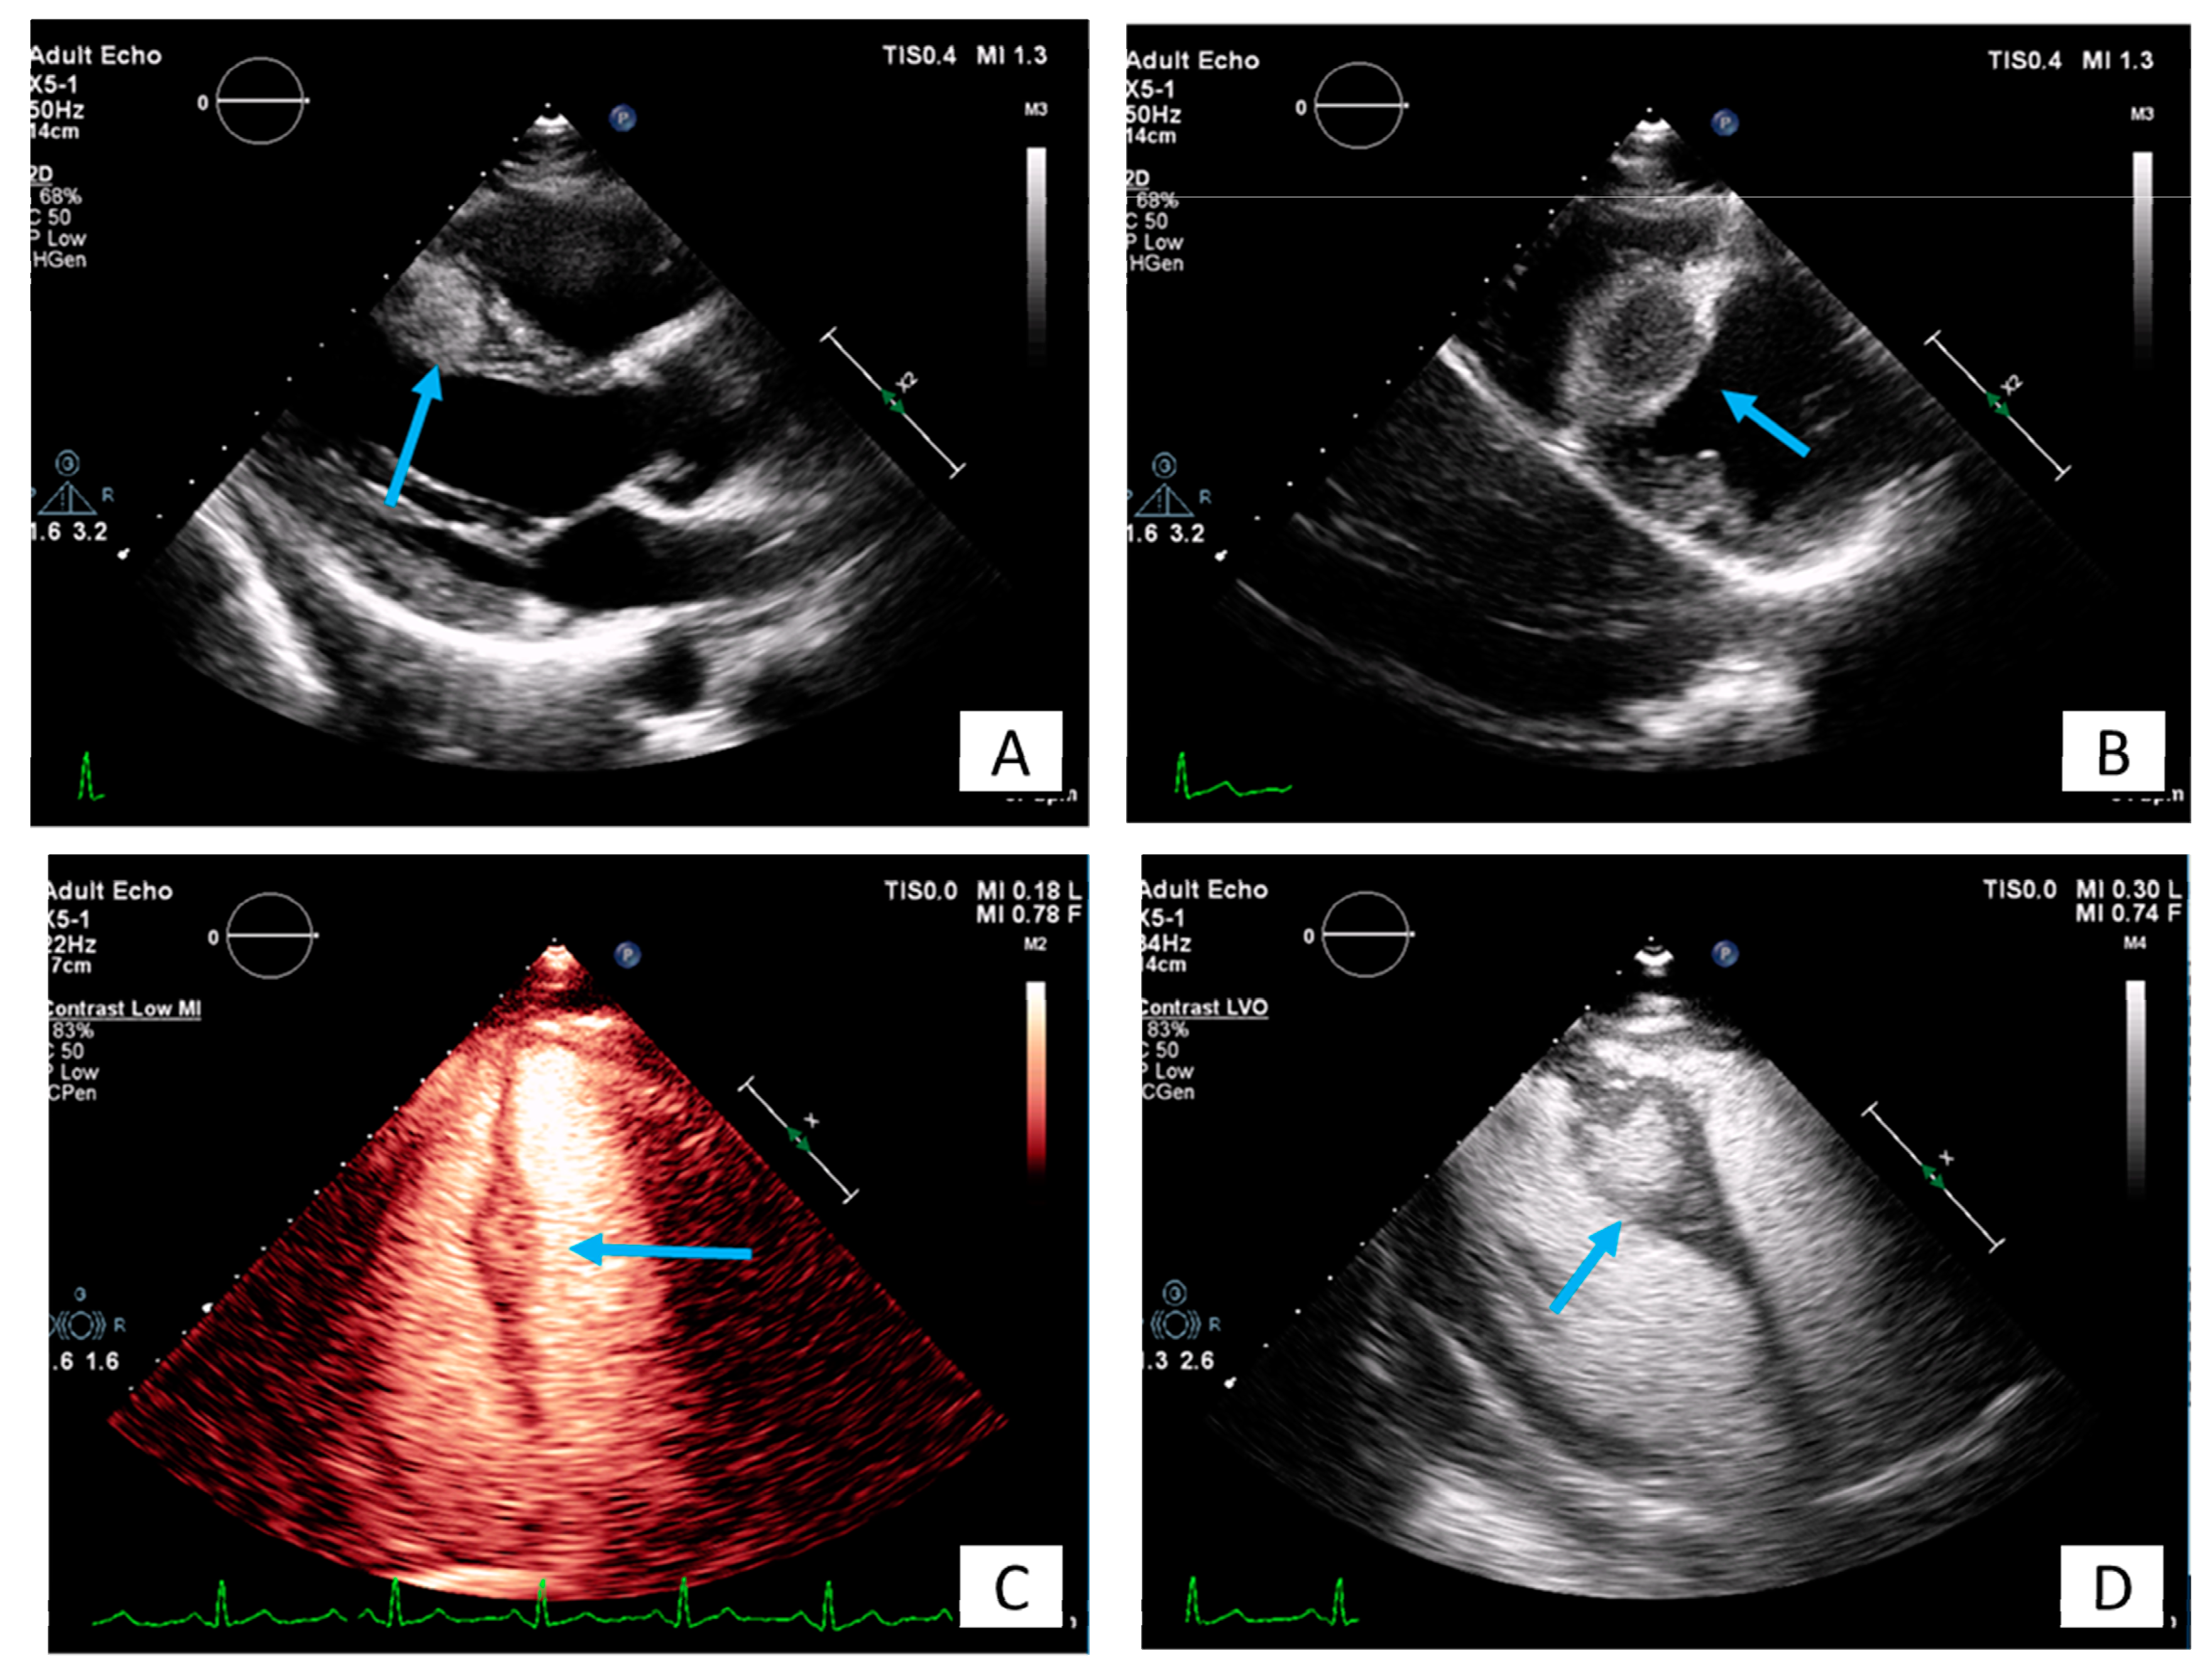

3.1. Transthoracic Echocardiography